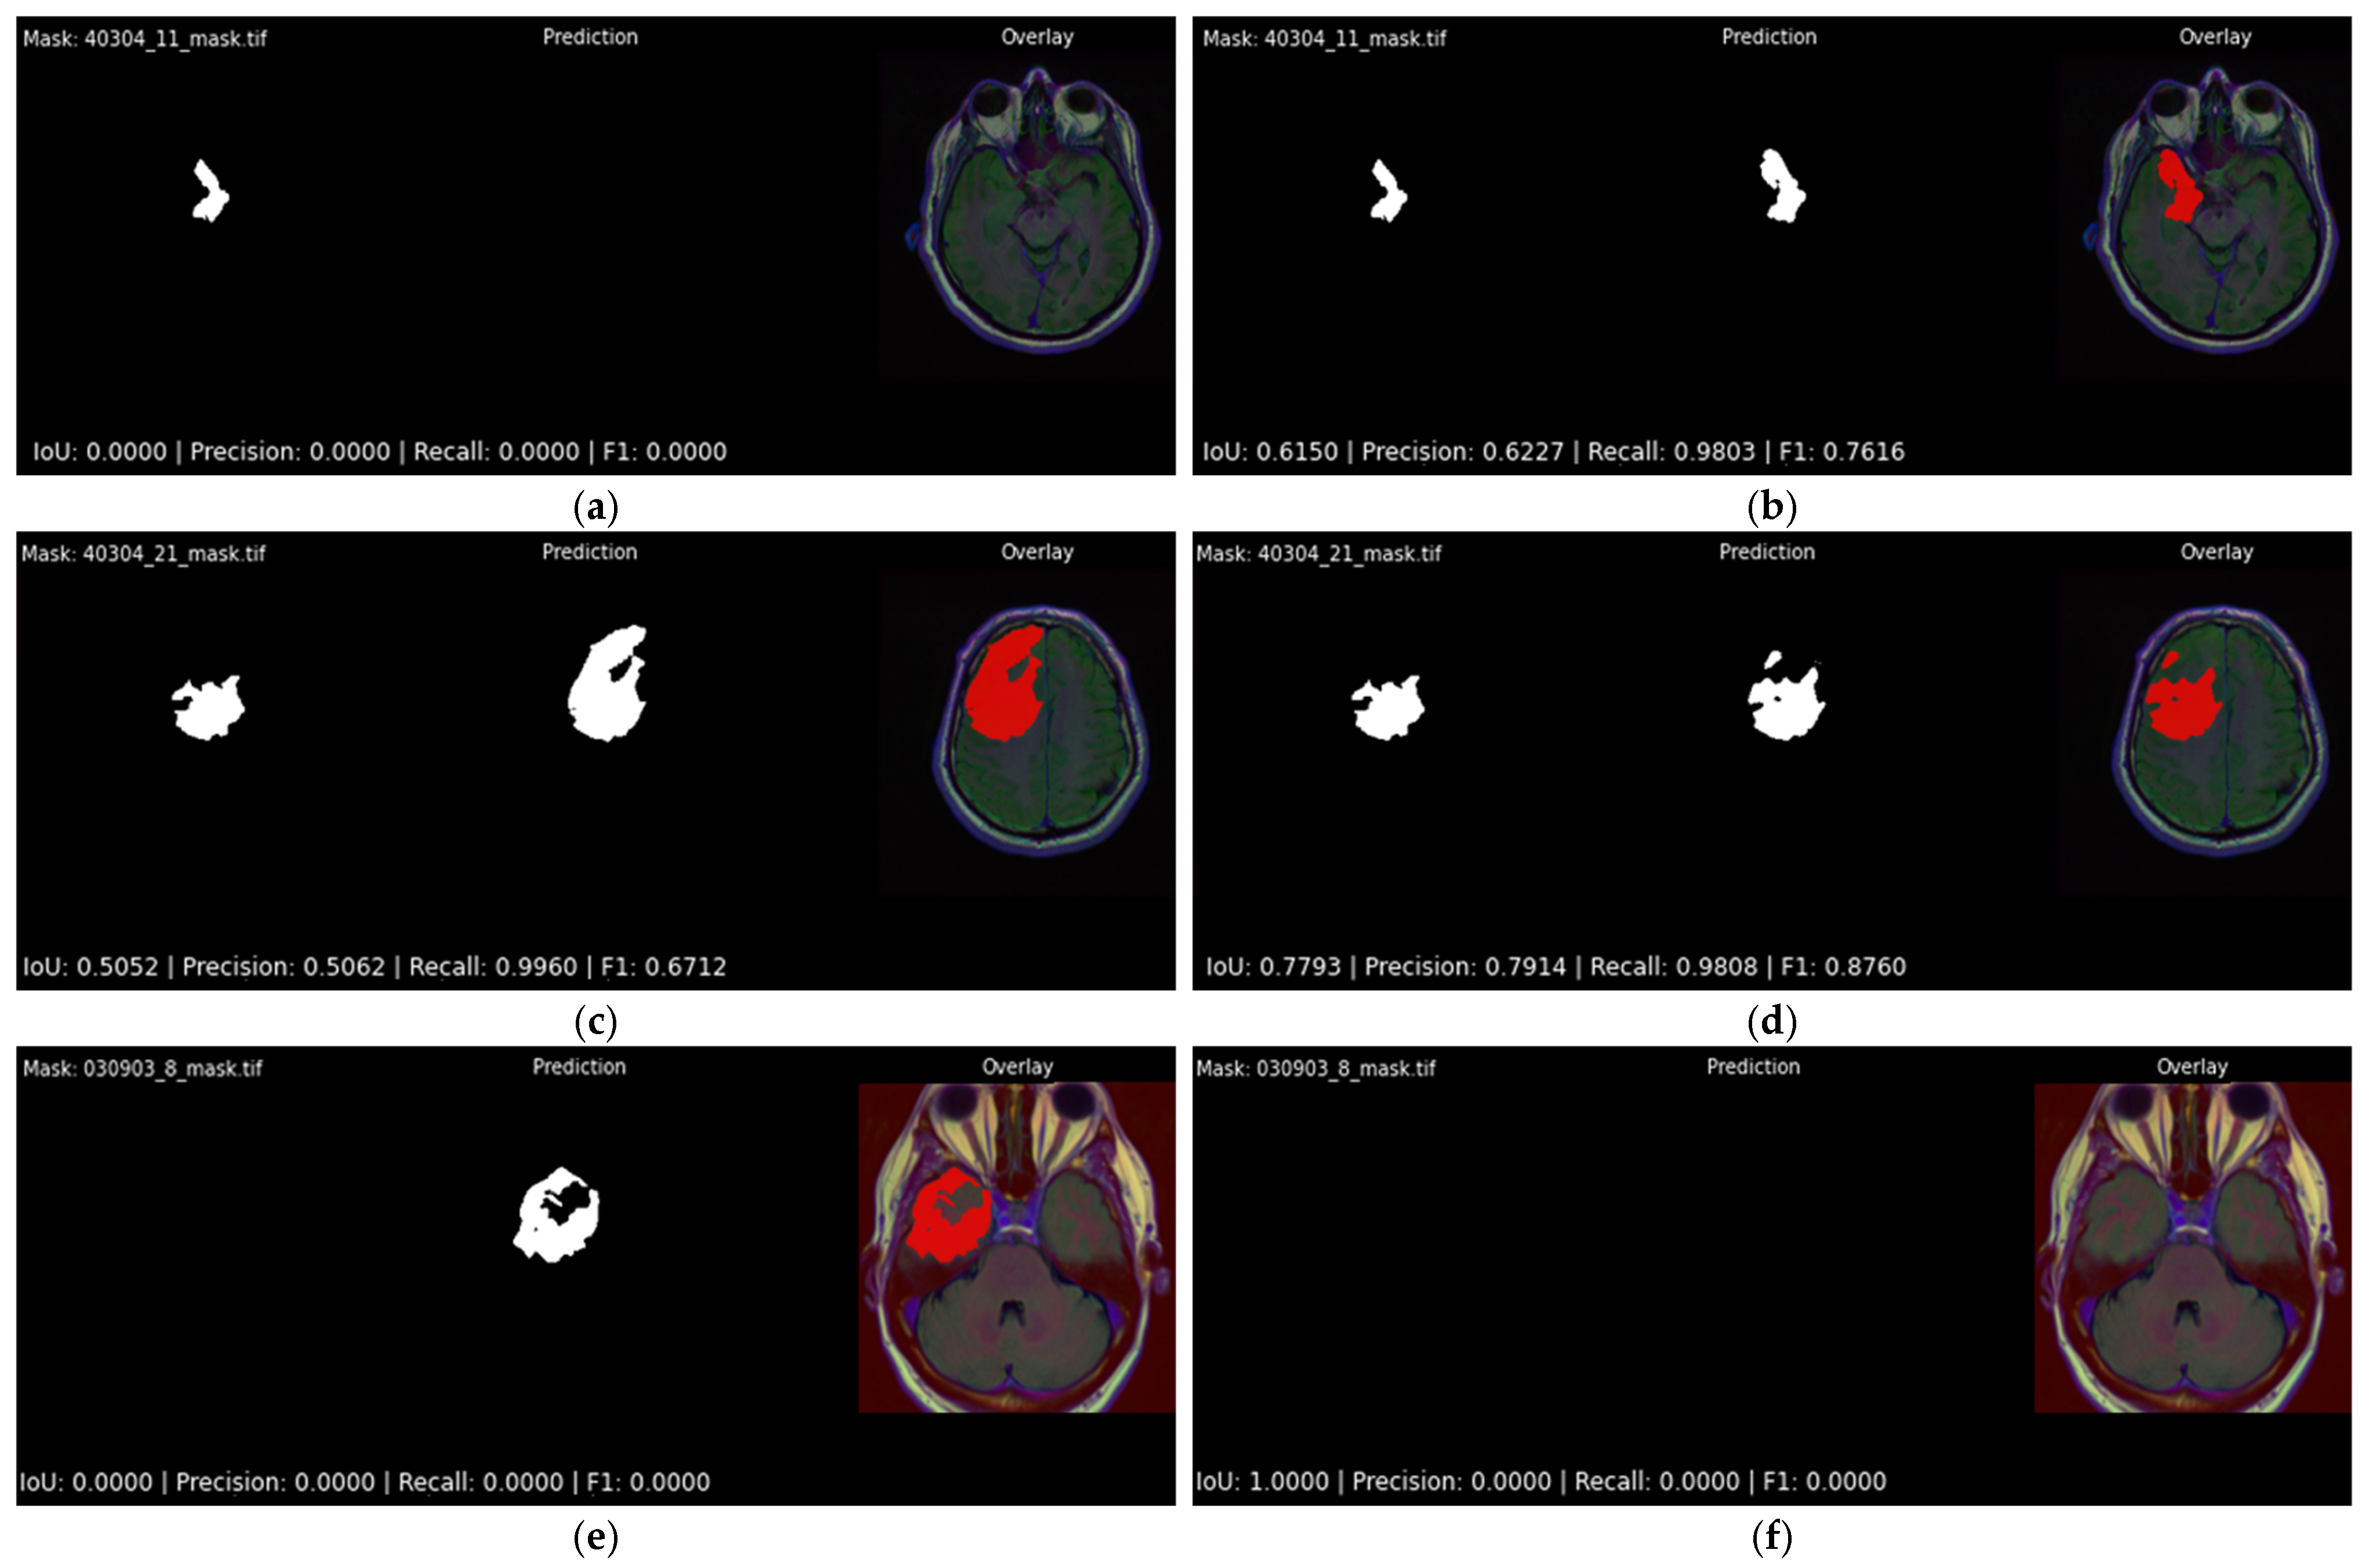

4.2. Qualitative Results

Figure 12 offers a side-by-side visual comparison of the two best-performing configurations as reported in Table 4 and Table 5, Attention U-Net trained with DiceBCE loss, under the two alternative output layers. The left column, Figure 12a,c,e, shows the sigmoid variant, while the right column, Figure 12a,c,e, shows the softmax variant. Each horizontal row represents the same patient, so differences between columns isolate the influence of the activation alone. The first row highlights a particularly challenging slice containing a very small lesion. The sigmoid model is unable to mark any overlapping pixels with the ground truth mask, which represents the worst possible detection outcome in a clinical setting (FN). The softmax model, although far from perfect, does identify part of the lesion and achieves an IoU of 0.615 (Figure 12b), demonstrating a clear practical advantage. The second row follows the same pattern: both models detect the bulk of the tumor, but the softmax head yields a noticeably higher overlap with the ground truth mask (IoU 0.779 versus 0.505). In the final row of Figure 12, where the ground truth mask does not contain any tumor pixels, the softmax variant accurately predicts this, whereas the sigmoid output falsely contains many tumor pixels. These examples confirm the quantitative finding that, although the two activations are statistically close, the softmax variant is less likely to fail catastrophically on difficult slices.

Figure 12.

Visual comparison of three difficult cases for the best-performing models with different output activation function layers. Each row showcases the results for the same patient case. Each subfigure showcases ground truth segmentation mask, predicted segmentation mask, and original image overlaid with the predicted segmentation output mask (red): (a,c,e) Attention U-Net paired with DiceBCE with sigmoid output; (b,d,f) Attention U-Net paired with DiceBCE with softmax output. Per-slice IoU, precision, recall and F1-score are reported beneath each overlay.